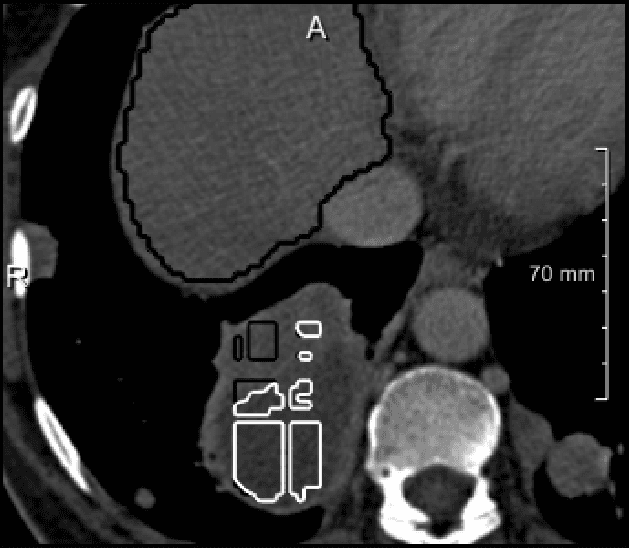

Abstract:Semantic segmentation neural networks require pixel-level annotations in large quantities to achieve a good performance. In the medical domain, such annotations are expensive, because they are time-consuming and require expert knowledge. Active learning optimizes the annotation effort by devising strategies to select cases for labeling that are most informative to the model. In this work, we propose an uncertainty slice sampling (USS) strategy for semantic segmentation of 3D medical volumes that selects 2D image slices for annotation and compare it with various other strategies. We demonstrate the efficiency of USS on a CT liver segmentation task using multi-site data. After five iterations, the training data resulting from USS consisted of 2410 slices (4% of all slices in the data pool) compared to 8121 (13%), 8641 (14%), and 3730 (6%) for uncertainty volume (UVS), random volume (RVS), and random slice (RSS) sampling, respectively. Despite being trained on the smallest amount of data, the model based on the USS strategy evaluated on 234 test volumes significantly outperformed models trained according to other strategies and achieved a mean Dice index of 0.964, a relative volume error of 4.2%, a mean surface distance of 1.35 mm, and a Hausdorff distance of 23.4 mm. This was only slightly inferior to 0.967, 3.8%, 1.18 mm, and 22.9 mm achieved by a model trained on all available data, but the robustness analysis using the 5th percentile of Dice and the 95th percentile of the remaining metrics demonstrated that USS resulted not only in the most robust model compared to other sampling schemes, but also outperformed the model trained on all data according to Dice (0.946 vs. 0.945) and mean surface distance (1.92 mm vs. 2.03 mm).

Abstract:Various approaches for liver segmentation in CT have been proposed: Besides statistical shape models, which played a major role in this research area, novel approaches on the basis of convolutional neural networks have been introduced recently. Using a set of 219 liver CT datasets with reference segmentations from liver surgery planning, we evaluate the performance of several neural network classifiers based on 2D and 3D U-net architectures. An interesting observation is that slice-wise approaches perform surprisingly well, with mean and median Dice coefficients above 0.97, and may be preferable over 3D approaches given current hardware and software limitations.